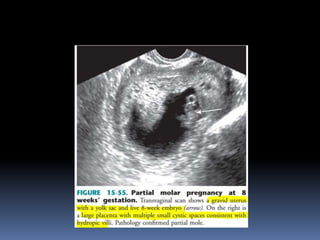

This document contains an image gallery from Dr. Mohit Goel showing various uterine anomalies and ovarian cysts. It includes images of an arcuate and unicornuate uterus, endometritis, a twisted ovarian pedicle, dermoid cysts of varying sizes and echogenicity containing hair, fat, and calcifications, and a combination dermoid cyst showing both mesh and plug structures. The gallery provides ultrasound images of different gynecological conditions for medical education and reference.